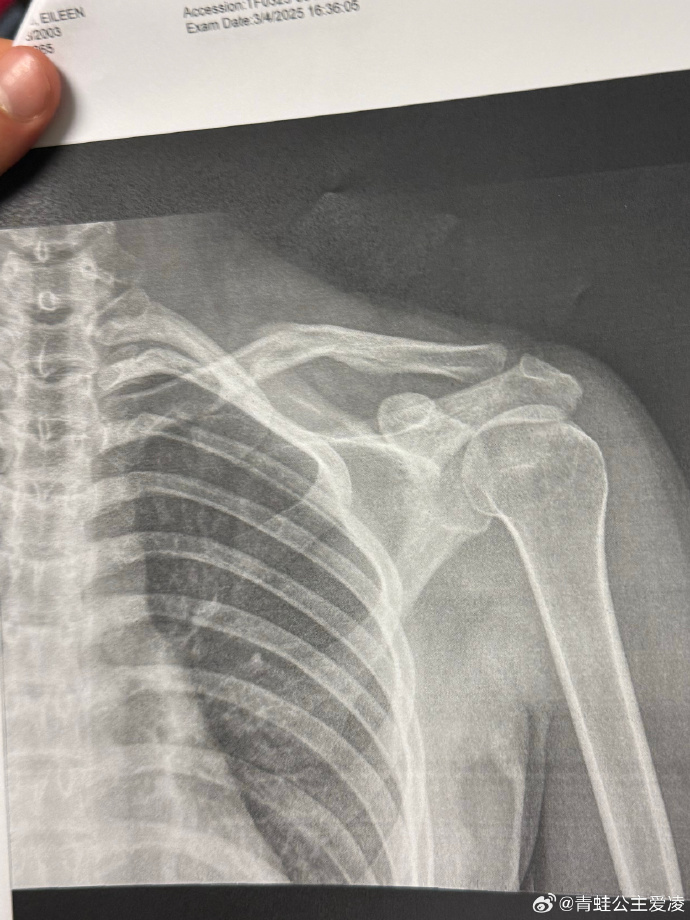

今年3月9日,谷爱凌在社交媒体晒出肩部骨折的X光照片,并配上一个心碎的表情,随后相关话题登上热搜。